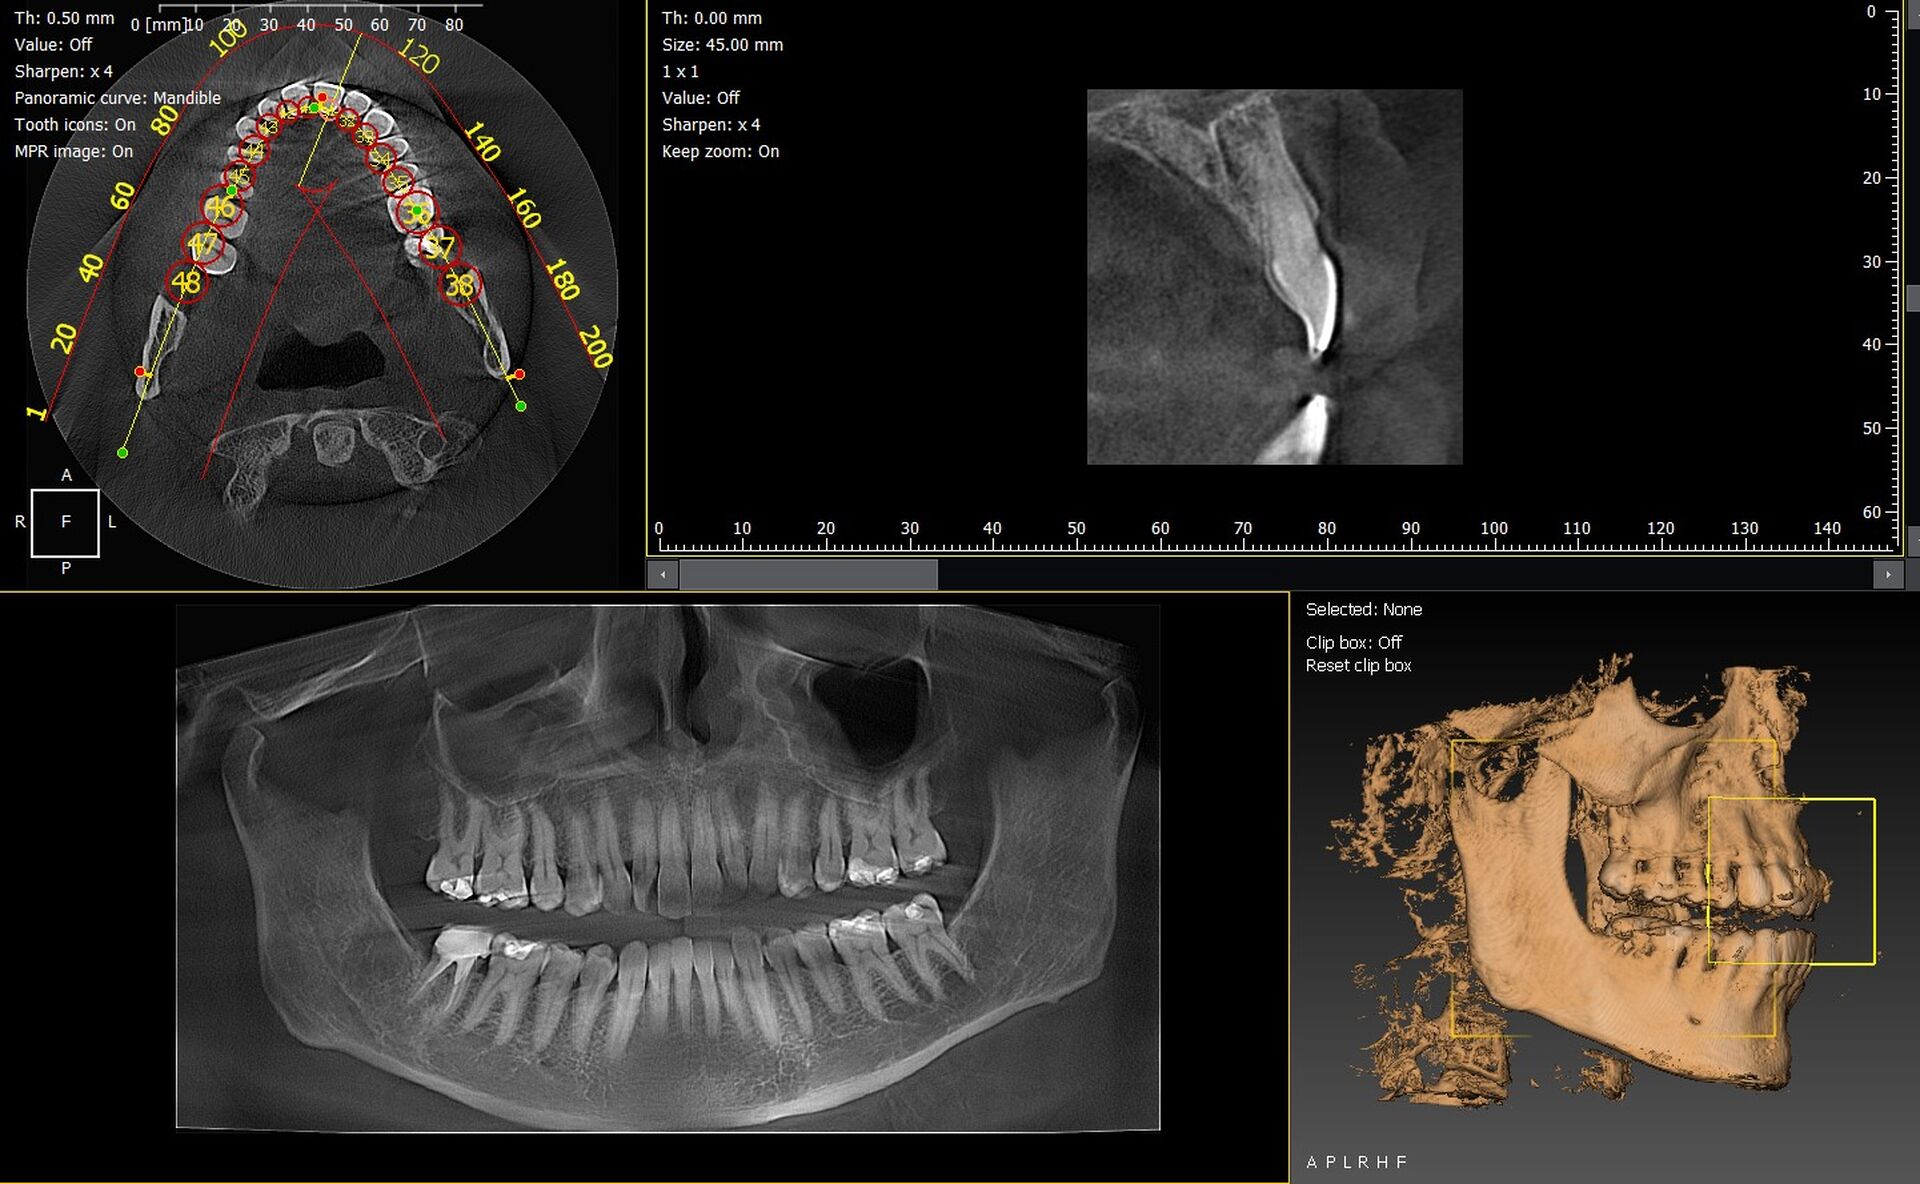

Les cabinets dentaires de Chorges et des Hautes Alpes 05 recherchent de plus en plus des solutions d’imagerie 3D capables d’améliorer le diagnostic, la précision clinique et la prise en charge des patients. Les systèmes CBCT permettent une visualisation complète des structures dentaires et osseuses, essentielle en implantologie, endodontie ou chirurgie orale. Parmi les références du marché, les gammes Durr Dental VistaVox et Owandy I-Max 3D offrent des performances élevées, une grande simplicité d’utilisation et une intégration facile dans les cabinets de Chorges.

Durr Dental VistaVox : un panoramique 3D CBCT pensé pour un diagnostic élargi

Le VistaVox se distingue par son volume 3D optimisé pour l’étude de l’arcade complète. Sa technologie permet d’obtenir des images précises des zones anatomiques complexes : nerf mandibulaire, sinus, jonctions dento-osseuses, racines et structures péri-apicales.